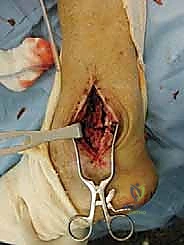

الخطوة الثانية: النهج الجراحي (Surgical Approach)

يتم فتح الشق الجراحي الأمامي القديم بحذر شديد لتجنب إتلاف الأوعية الدموية والأعصاب، وهنا تبرز أهمية تقنيات الجراحة الميكروسكوبية التي يتقنها الدكتور هطيف.

الخطوة الثالثة: إزالة المفصل القديم (Explant Removal)

يتم استخراج المكونات المعدنية والبلاستيكية لمفصل (Agility) القديم بحرص بالغ للحفاظ على ما تبقى من العظم السليم.